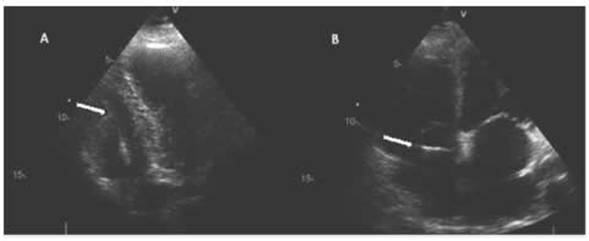

Todos los procedimientos fueron realizados en posición supina bajo monitoreo electrocardiográfico (ECG). El procedimiento para obtener las muestras de biopsia fue llevado a cabo por el mismo operador. El acceso al corazón fue realizado por punción de la vena yugular interna derecha luego de la administración de anestesia y antisepsia local, colocándose un introductor. La correcta punción de la vena mencionada y la posición del introductor se controló mediante la inyección de 5 ml de solución fisiológica y la visualización de burbujas en cavidades derechas mediante ecocardiografía bidimensional. Se insertó luego el biótomo de Schultz Caves de 8 o 9 French o un biótomo descartable Cordis Bipal de 7 French. El avance del biótomo fue controlado por ecocardiografía 2D a través de la aurícula derecha y la válvula tricúspide (Figura 1).

El biótomo se abría en el ventrículo derecho y se identificaba el contacto mediante control ecocardiográfico de la punta con el endocardio. La toma de biopsia se efectuaba mediante el cierre de la pinza y se extraía la muestra de miocardio, procedimiento que se repetía de 5 a 10 veces.